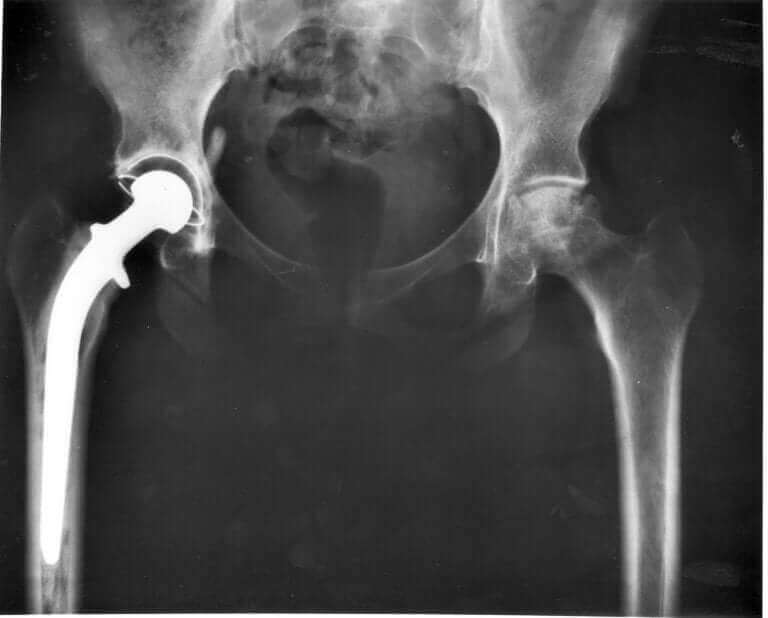

Veterinæren din må se på hofteleddene til katten din og ta bekkenrøntgenbilder for å identifisere det nøyaktige problemet. Hvis katten din faktisk har hofteleddsdysplasi, finnes det noen behandlinger for å gi den lettelse og bremse symptomene. Dessverre er det fortsatt ingen kur.

Noen av disse behandlingene inkluderer ting som fysioterapi, begrensning av visse aktiviteter, betennelsesdempende medisiner (oralt eller injisert) og vektovervåkning. I mer alvorlige tilfeller kan den trenge en hofteutskiftningsoperasjon.